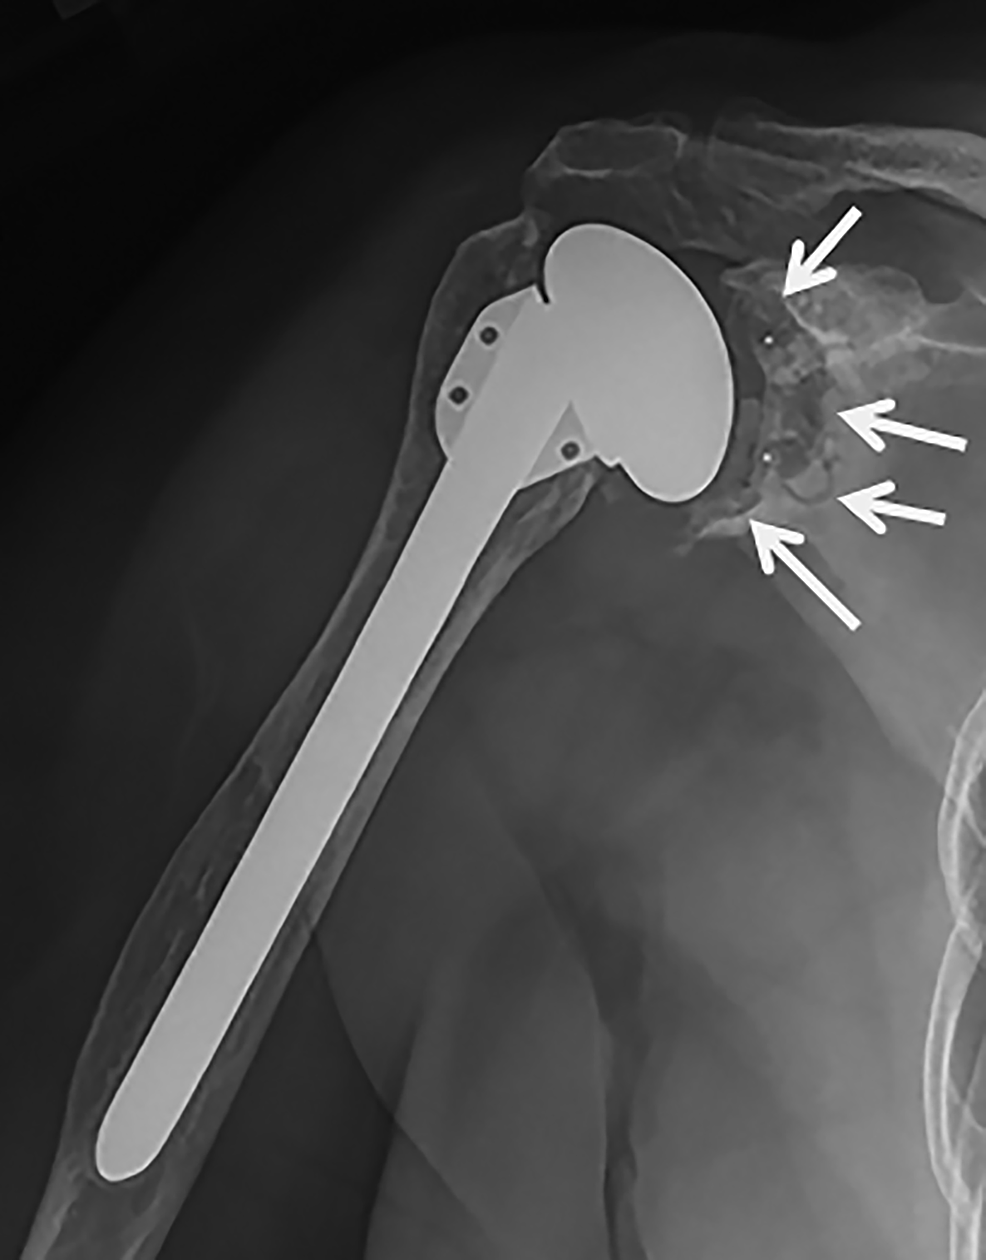

From musculoskeletalkey.com

Chapter 15 Reverse Shoulder Arthroplasty in Revision Shoulder How Difficult Is Shoulder Replacement Shoulder replacement surgery is an option given to patients who suffer from joint dysfunction. It’s difficult to say just how long your shoulder replacement will last. There are many options, ranging from. Knowing what to expect after shoulder replacement can help you prepare physically and mentally. When arthritis or pain in your shoulder becomes severe enough to affect your daily. How Difficult Is Shoulder Replacement.

From mungfali.com

Left Reverse Total Shoulder Arthroplasty How Difficult Is Shoulder Replacement It’s difficult to say just how long your shoulder replacement will last. There are many options, ranging from. Learn more about the procedure, risks, recovery time, and what to. Shoulder replacement surgery is an option given to patients who suffer from joint dysfunction. This is usually the result of osteoarthritis, rotator cuff tear arthropathy, avascular. When arthritis or pain in. How Difficult Is Shoulder Replacement.